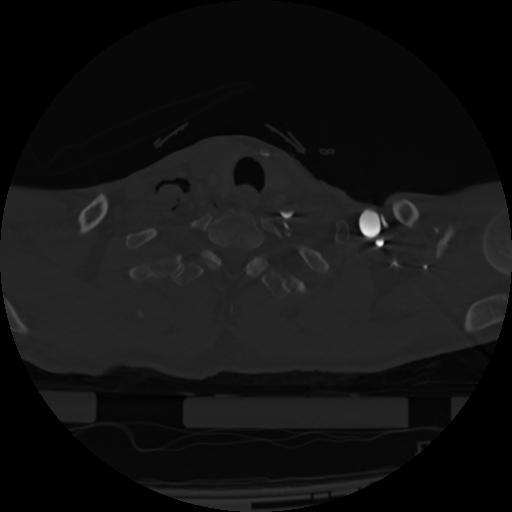

22 ANGIO,CE,Vol,0.5,ANGIO,,